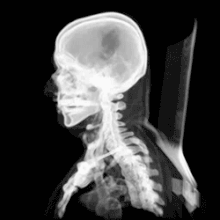

Череп человека

Разница между черепом человека и человекообразных обезьян заключается прежде всего в том, что человеческий череп по своей форме приспособлен к прямохождению. Голова балансирует на позвоночнике, из-за чего шейная мускулатура менее развита, а сам череп тоньше. Передняя часть черепа у человека более плоская, а объём краниальной полости значительно больше, для того, чтобы в него вмещался расширившийся в объёме мозг.